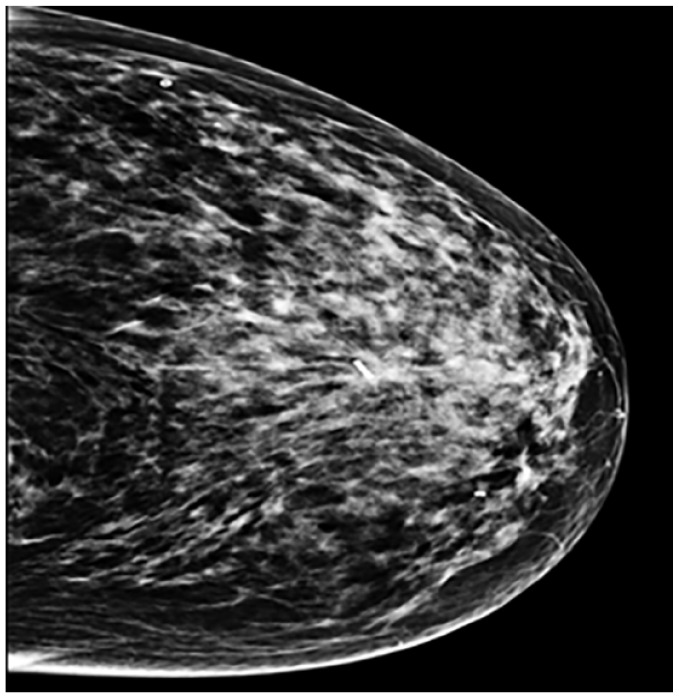

Design and methods: Forty-seven patients with non-palpable breast lesions, who underwent Magseed pre-operative localization followed by breast-conserving surgery between November 2022 and June 2024 at our Breast Unit were enrolled in our study. The procedure involved percutaneous placement of the Magseed into the target lesion under ultrasound (66%) or stereotactic (34%) guidance. Data on patient demographics, lesion characteristics, Magseed localization and retrieval, surgical outcomes, and complications were collected and analyzed.

Abstract Image